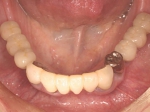

メタルボンド症例

治療前治療前主訴-前歯部の咀嚼不全と審美障害。ブリッジ(固定橋義歯)のために歯を削ったところ 作業模型上のブリッジ作業模型上のブリッジ作業模型上のブリッジ 口腔内装着口腔内装着口腔内装着